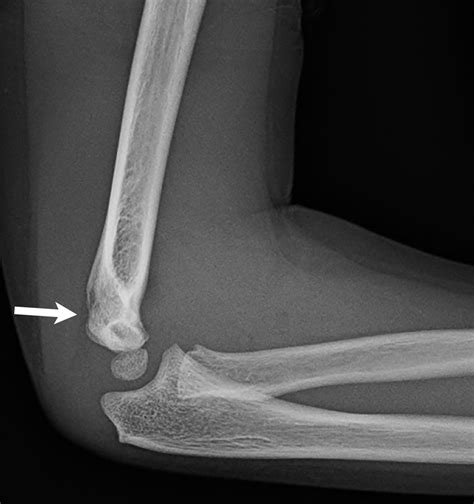

Diagnosing a Medial Epicondyle Fracture

Diagnosing a Medial Epicondyle Fracture involves a combination of physical examination and imaging tests. The diagnostic process typically includes:

• Physical Examination: The healthcare provider will assess the elbow for swelling, tenderness, and range of motion. They may also check for any deformities or instability in the joint.

• Imaging Tests: X-rays are the primary imaging tool used to diagnose a Medial Epicondyle Fracture. They can reveal the location and extent of the fracture. In some cases, additional imaging such as a CT scan or MRI may be required to provide a more detailed view of the injury.

Accurate diagnosis is crucial for determining the appropriate treatment plan.